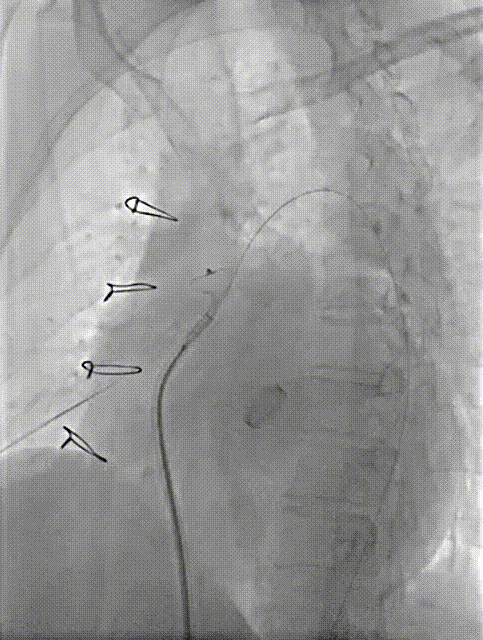

术中操作

2.Aortic Wrapping吻合口漏位置多有不同,常见的是冠脉吻合口位置和升主动脉人工血管与自体远端血管吻合口位置,少数患者合并人工瓣膜瓣周漏。因此,此类手术是典型的不定型手术,特别是对于拟行微创封堵手术患者,术前多模态影像评估,尤其是3D打印实物模型对于手术方案制定有重要意义。

4.对于Aortic Wrapping吻合口漏,应优选入口出口双伞封堵,有利于术后包裹腔快速机化消除分流。